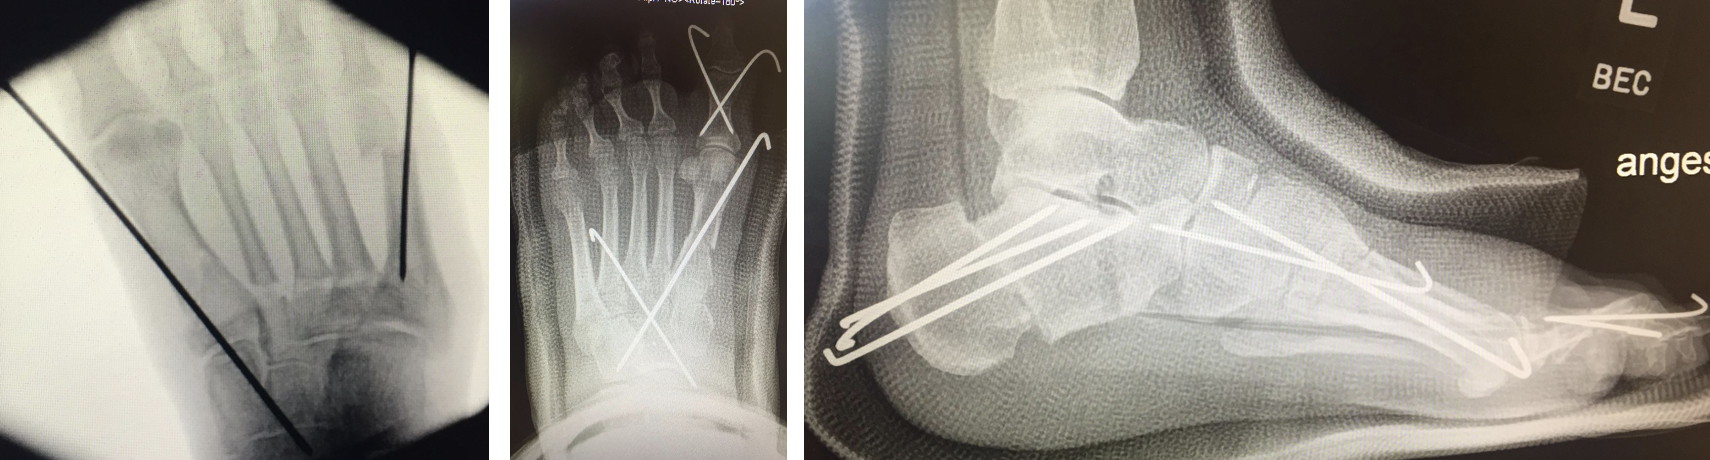

Abb. 2 a-c: offene Wachstumsfugen MT I Basis und Zehen (a), teilweise geöffnete Wachstumsfugen (b) und geschlossene Wachstumsfugen (c).

Zum Lesen der Bildbeschreibung und zur Vollansicht bitte die Bilder anklicken. Bilder: A. Helmers.